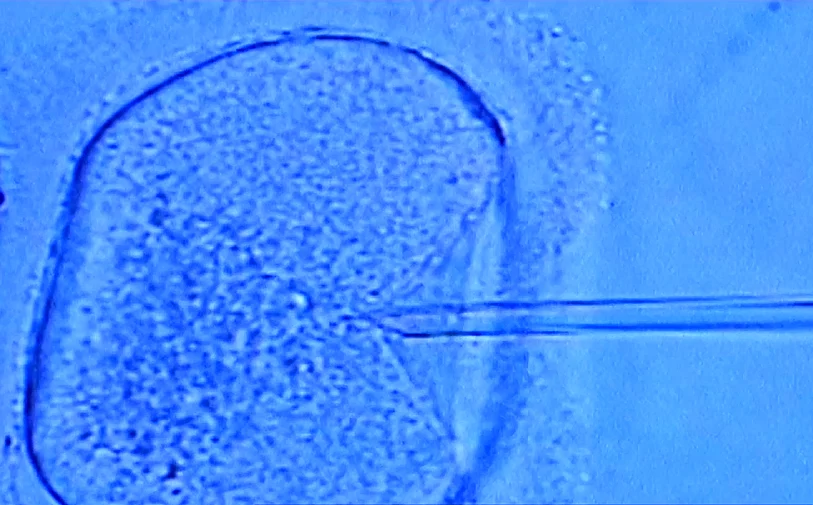

ארה"ב: זוג מניו יורק תבע את מרפאת הפוריות בה טופלו, לאחר שבשל טעות בטיפולי ההפרייה, ילדה האישה תאומים השייכים לזוג אחר. האם, ממוצא אסיאתי, ילדה זוג תאומים שאינם אסיאתים, וכל אחד מהם מתאים גנטית לזוג אחר שהשתמש בשירותי המרפאה, כך נכתב בתביעה. הזוג האסיאתי נאלץ לוותר על שני הילדים שנולדו להם, ולמסור אותם להורים הביולוגיים שלהם.

על פי כתב התביעה, הזוג שילם מעל 100 אלף דולרים עבור טיפולי ההפרייה, שבסופם הודיעה המרפאה כי הצליחו להפרות חמישה עוברים תקינים - ארבע נקבות וזכר אחד.

לאחר שהניסיון הראשון להחזיר את העוברים לרחם האישה כשל, התרגשו הזוג לגלות כי היא סוף סוף בהיריון. אך בעת בדיקת האולטראסאונד, התברר להורים כי האישה נושאת שני תאומים זכרים. הדבר גרם לבלבול, משום שכאמור רק אחד מהעוברים שהופרו היה זכר – וגם הוא לא הוחזר לרחם האישה. כשפנה הזוג אל בעלי המעבדה, נאמר להם שבדיקות האולטרסאונד אינן חד משמעיות.